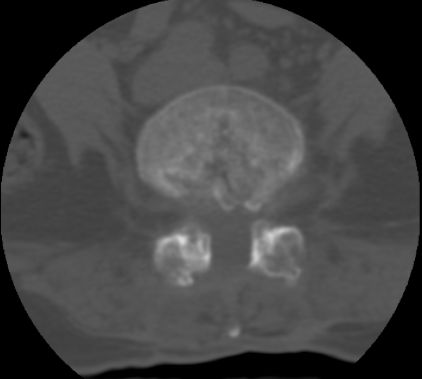

以下是引用余辉在2007-9-4 21:00:00的发言:[br]椎体棘突有点异常(像是被切割了),不知有否手术史,如椎体融合术等。单纯的退行性变可以出现椎间隙变窄,但同时一般会出现椎体上下缘的硬化增生,且椎体间完全融合的机率更小,本例椎体完全融合且椎体上下皮质缘破坏掉了,如果没有手术史,就应该考虑椎间盘炎性病变了,且椎体棘突及棘间韧带的变化也并不是不支持这个,多数小关节也融合了,且其形态也容易让人联想到如强脊炎及类风关等病变。[br][br][本贴已被 余辉 于 2007-9-4 21:03:55 修改过]

以下是引用chry3在2007-9-4 20:42:00的发言:[br]椎间盘病史?是什么样的病史,无双下肢放射痛,那就不是椎间盘突出了。是感染、什么性质的?[br]从图象看椎间隙消失,椎间盘组织未见,锥体滑脱是因为椎间盘溶解造成的[br]l4、5椎体骨质结构未见异常,l5上缘是l4的长期压迫所致[br]还是考虑椎间盘感染,结核。[br]